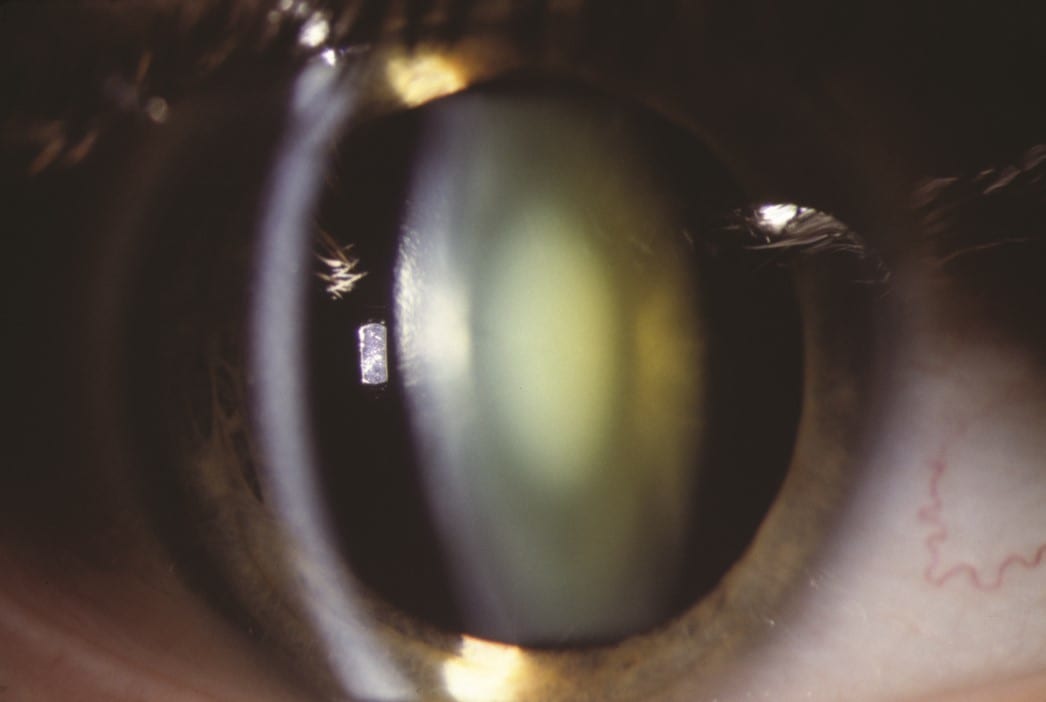

Cataract Surgery

State-of-the-art cataract extraction technique with placement of a mono- or multifocal intraocular lens.